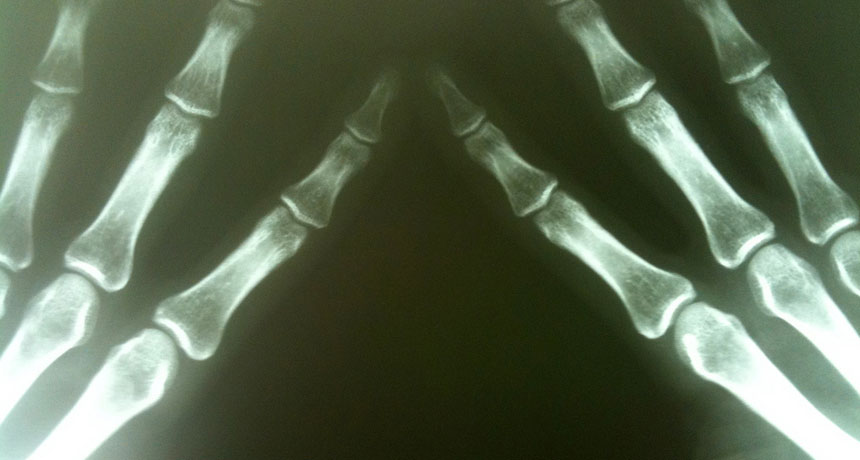

X-rays allow us to see our bones in wonderful detail. But too much exposure can be dangerous. X-rays are a carcinogen, meaning that they can cause cancer.

Michael Dorausch/Flickr/(CC BY-SA 2.0)